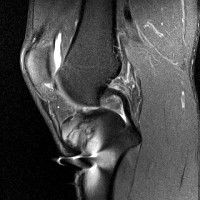

무릎 mri 간단히 봐주실 수 있으시나요 ㅠㅠ

안녕하세요 8년전 십자인대 수술하고 최근 무리한 운동에 무릎 불편감이 생겨서

mri 찍었습니다.

진단결과는 첫 찍은 병원에서 활액막염 이라는 진단을 받았습니다. 혹시 봐주실 수 있으실까요?

• 안녕하세요. 강성주 의사입니다.

올라온 MRI가 단편적이라서 정확한 진단에 어려움이 있지만 십자인대에는 큰 이상이 있지는 않은것 같으며, 무릎관절내 물이 있는 것으로 보아 활액막염의 진단이 맞을 것 같습니다.

하지만 단편적인 영상이기 때문에 촬영병원에서 정확한 판독지 등을 받으시는 것이 좋겠습니다.